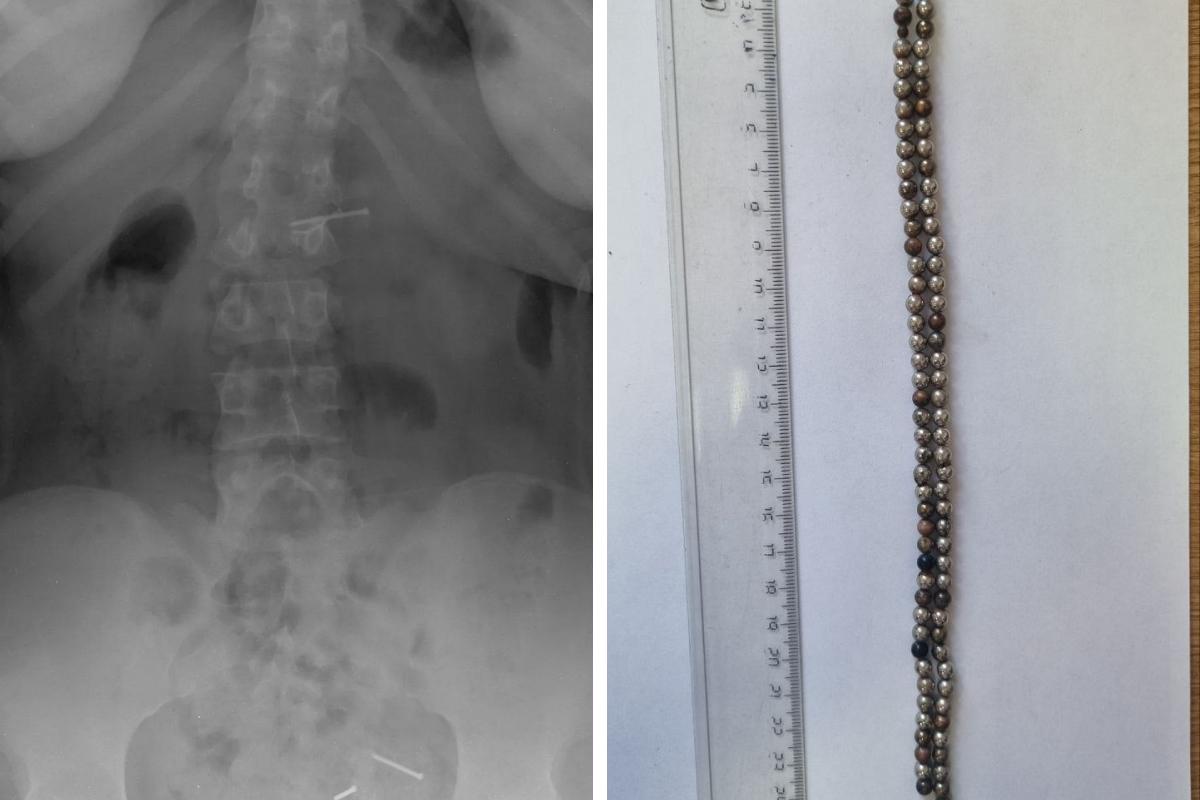

Евгения Аверкина пояснила: «Обследование выявило множественные рентгенконтрастные предметы в кишечнике и явные признаки кишечной непроходимости. В ходе экстренной операции было удалено 25 магнитов».

Магниты могут притягиваться через стенки кишечника, вызывая непроходимость, некроз, перфорацию и образование свищей. Установлено, что 25 магнитов находились в организме ребенка продолжительное время, что привело к серьезным последствиям. Операция прошла успешно, и в настоящее время его жизни ничто не угрожает.